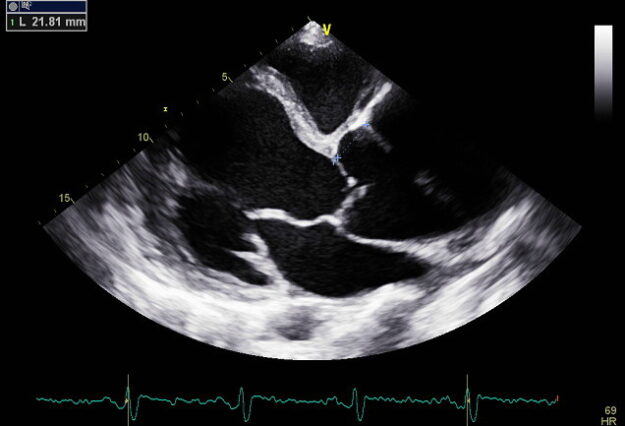

A double quadri in a week! Quadricuspid aortic valve is an extremely rare finding on echocardiography. The incidence is 0.0059-0.0065% for patients undergoing transthoracic echocardiographic examinations. Presenting two successive cases seen in two successive weeks in our echo lab! Your browser does not support the video tag. Your browser does not support the video tag.…